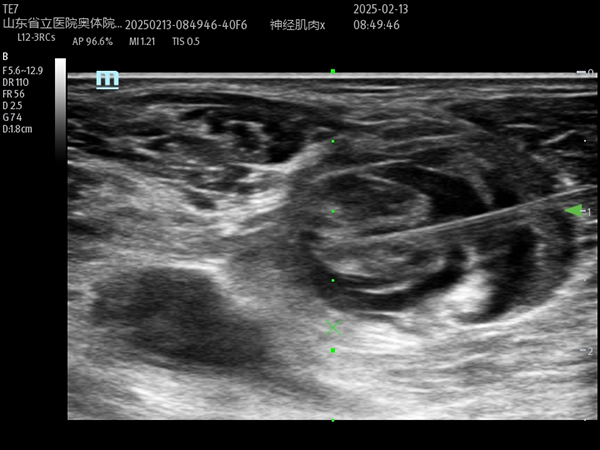

麻醉手术科副主任医师李旺在副主任医师马金本和医师刘聪协助下,在超声引导下精准完成了右腿的髂筋膜阻滞和腘窝坐骨神经阻滞,经过测试阻滞后镇痛效果良好。考虑到患者一般状态较差若同时进行两侧下肢神经阻滞,有发生局麻药中毒风险,遂在右腿清创手术完成后,再行左下肢的超声引导下阻滞术,保证了患者的安全、麻醉镇痛效果和手术的顺利进行。

超声引导下右侧下肢腘窝坐骨神经阻滞